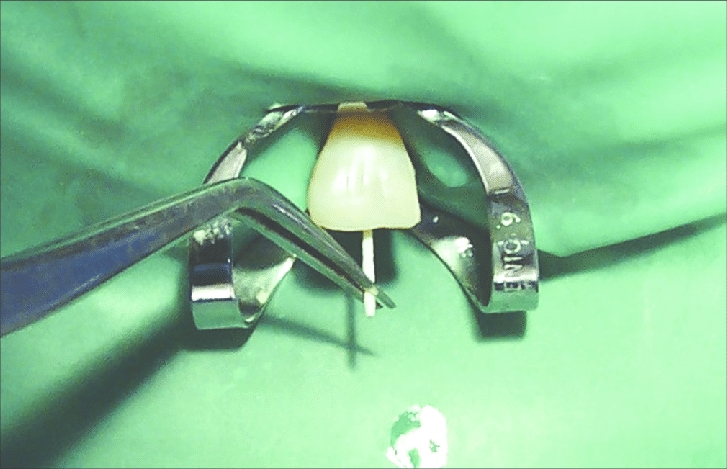

Root Canal Treatment: Diapex Plus, Diapaste, Dia-Root Bio MTA.